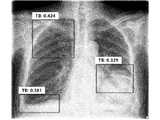

도 8 및 도 14는, 이미지 콘솔 뷰어부(200)가 생성한 의료 영상에 대해서 영상 판독부(300)가 판독한 결과를 태그 정보를 추가한 저장한 다이콤 파일 형태의 의료 영상을 일반 다이콤 뷰어를 사용하여 나타낸 것이다.8 and 14 show a medical image in the form of a daicom file in which tag information is added to the result of reading the medical image generated by the

도 8은, 도 7의 의료 영상에 대한 영상 판독부(300)의 판독 결과에 대한 태그 정보가 바운딩 박스 안에 도시한 바와 같이 저장되어 있음을 나타낸 것이다.FIG. 8 shows that tag information on the reading result of the

도 9 및 도 15는 의료 영상에 대한 판독 결과로서 바운딩 박스를 이미지에 중첩하여 나타낸 것이며, 도 10 및 도 16은 윤곽선맵 (Contour Map)을 이미지에 중첩하여 나타낸 것이며, 도 9 및 도 17은 히트 맵(Heat Map)을 이미지에 중첩하여 나타낸 것이며, 도 12 및 도 18은 검출 점수(Screening Score)을 이미지와 함께 나타낸 것이다.9 and 15 are a reading result of a medical image, showing a bounding box superimposed on an image, FIGS. 10 and 16 are showing a contour map superimposed on an image, and FIGS. 9 and 17 are hits A map (Heat Map) is shown by superimposing it on an image, and FIGS. 12 and 18 show a detection score (Screening Score) with an image.

한편, 도 19는 의료 영상에서 영상 판독부(300)가 복수개의 병변에 대해 판독한 결과의 일예를 나타낸 것이며, 이는 태그 정보를 병변의 수만큼 추가로 생성하여 프라이빗 다이콤 태그에 저장할 수 있음을 나타낸 것이다.Meanwhile, FIG. 19 shows an example of a result of the

또한, 도 20은 의료 영상에 대한 영상 판독부(300)의 복수개의 검출결과로 복수개의 바운딩 박스를 이미지에 중첩하여 나타낸 일 예이다. 이 또한 바운딩 박스의 수 만큼 바운딩 박스의 좌표, 병변명 및 검출 확률 등을 태그 정보에 추가로 저장할 수 있음을 나타낸 것이다.Also, FIG. 20 is an example showing a plurality of detection results of the

판독 결과는 도 7 내지 도 20에 예시된 바와 같이 다양한 형태로 나타낼 수 있다. 검출확률 또는 점수(Screening Score), 바운딩 박스의 좌표정보, 클래스명 및 분류 확률, 윤곽선 맵의 좌표 정보 및 윤곽선 맵 개수, 클래스명, 히트 맵 픽셀 어레이 사이즈 정보 및 픽셀 값 등으로 표시가 된다.The reading result may be displayed in various forms as illustrated in FIGS. 7 to 20 . Detection probability or score, coordinate information of bounding box, class name and classification probability, coordinate information of outline map and number of outline maps, class name, heat map pixel array size information and pixel value are displayed.